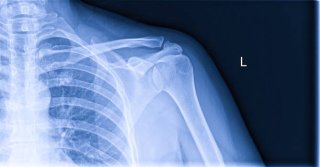

3. 어깨통증 원인 - 석회성 건염

어깨통증 원인 중 통증이 갑자기 심해지는 대표적인 질환이 석회성 건염입니다. 이는 어깨 힘줄에 칼슘이 침착되어 돌처럼 굳는 상태를 말합니다.

석회가 쌓이면 염증 반응이 심해져 갑작스러운 극심한 통증이 발생하며, 팔을 거의 들지 못할 정도가 됩니다.

특징적으로 밤에 통증이 심하고, 자려고 누우면 어깨가 욱신거리거나 찌르는 듯 아픕니다. 엑스레이나 초음파 검사로 쉽게 확인할 수 있으며, 체외충격파나 주사치료로 비교적 잘 치료됩니다.